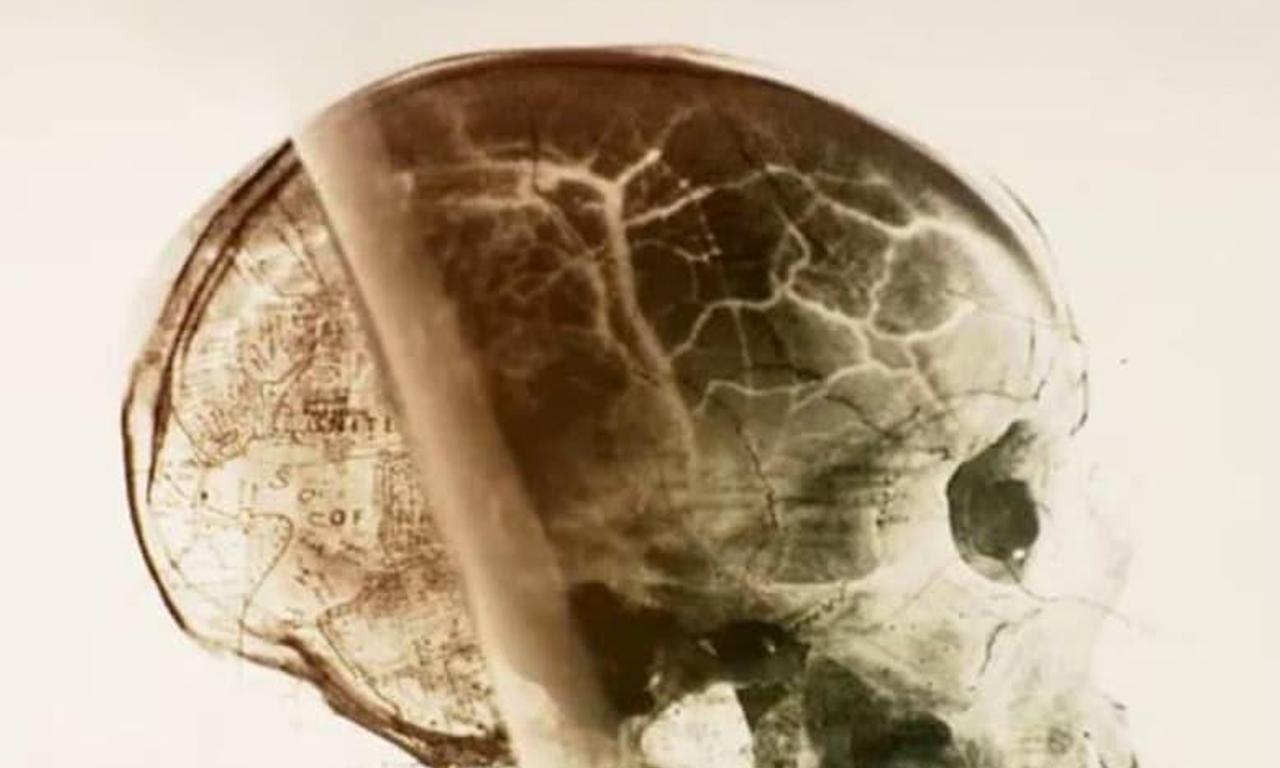

Brothers Jim and Bill Vieira search for giant skeletons after researching tales of giants being sighted along with old accounts of giant bones being uncovered across the country.